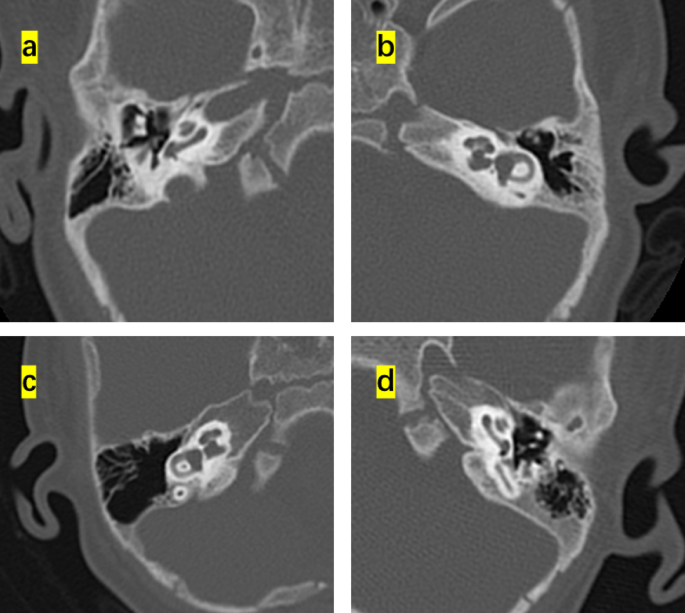

This study enrolled 16 children (8 months to 4 years old) that were diagnosed with diverse phenotypes of syndromic hearing loss and underwent CI. These included six, three, one, and six cases of WS, NS, KS, and CS, respectively. Children with different types of NCP-based hearing loss exhibit unique facial features: the iris of children with WS were heterochromic, and there were no abnormalities in the head and facial structure; the patients with NS had protruding foreheads, widened eye distances, and downward inclination of the eye fissures; the patient with KS had cracks on the long eyelid, with a slight outward rotation of one-third of the lower eyelid and a cup-shaped ear on the right side; all the CS patient were with predominant craniofacial anomalies involving the ears and eyes. Table 1 shows the main clinical features of the 16 children, specifically highlighting the ear malformations and the degree of developmental delay. There were observable differences between the types of syndromic hearing loss. WS and NS showed mild malformations of the middle and inner ear (Figs. 1 and 2). KS (Fig. 3) primarily exhibited malformations of the outer and middle ear structures. CS (Fig. 4) showed significant malformations in the outer, middle, and inner ear and showed varying degrees of stenosis or occlusion of the cochlea in different cases (Fig. 5). Cochlear nerve canal stenosis was observed in almost every CS case. Apart from WS, the other three syndromes showed clear craniofacial malformations, growth delay, and varying degrees of neurodevelopmental delay. Gesell scores were below the normal value of 85. Among the syndromes, WS and NS exhibited mild symptoms, KS showed more pronounced symptoms, and CS cases were the most severe.